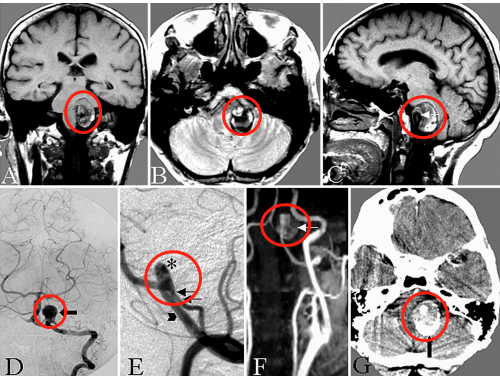

47歲的陳先生在家中突然感到劇烈頭痛,隨即陷入昏迷。家人緊急送醫(yī)后,急診CT檢查給出了令人揪心的結(jié)果:彌漫性蛛網(wǎng)膜下腔出血(圖A),而進(jìn)一步的血管造影揭開了真兇...... CT顯示彌漫性蛛網(wǎng)膜下腔出血,左側(cè)腦橋前池增厚明顯。 陳先生47歲動脈瘤 病情階段: 出血后第18天,待陳先生狀況穩(wěn)定后,...

47歲的陳先生在家中突然感到劇烈頭痛,隨即陷入昏迷。家人緊急送醫(yī)后,急診CT檢查給出了令人揪心的結(jié)果:彌漫性蛛網(wǎng)膜下腔出血(圖A),而進(jìn)一步的血管造影揭開了“真兇”......

CT顯示彌漫性蛛網(wǎng)膜下腔出血,左側(cè)腦橋前池增厚明顯。

出血后第18天,待陳先生狀況穩(wěn)定后,醫(yī)生進(jìn)行了腦血管造影檢查(圖B)。結(jié)果顯示,左側(cè)大腦后動脈P1-P2段出現(xiàn)異常擴(kuò)張伴狹窄——這是夾層動脈瘤的特征表現(xiàn)。

出血后18天血管造影顯示左側(cè)P1-P2段擴(kuò)張伴狹窄特征,顳后動脈自狹窄病變遠(yuǎn)端發(fā)出(箭頭標(biāo)注)

醫(yī)生通過左側(cè)顳下入路,選擇后顳動脈作為受體(圖C、D),成功完成搭橋和孤立術(shù),整個手術(shù)過程如同在“萬丈懸崖邊繡花”,每一步都要求精準(zhǔn)到毫米,既要避免損傷周圍神經(jīng)和血管,又要保證吻合口毫無滲漏。

C、D.選擇顳后動脈(箭頭標(biāo)注)作為受體動脈,經(jīng)左側(cè)顳下入路用連續(xù)縫合行顳淺動脈-顳后動脈吻合;

術(shù)后1周復(fù)查頸外動脈血管造影顯示,通過新建的分流血管,左側(cè)大腦后動脈供血區(qū)血流完全通暢(圖E箭頭標(biāo)注),沒有出現(xiàn)任何缺血跡象。

術(shù)后1周頸外動脈血管造影顯示,通過分流血管,整個左側(cè)大腦后動脈供血區(qū)血流良好(箭頭標(biāo)注)。